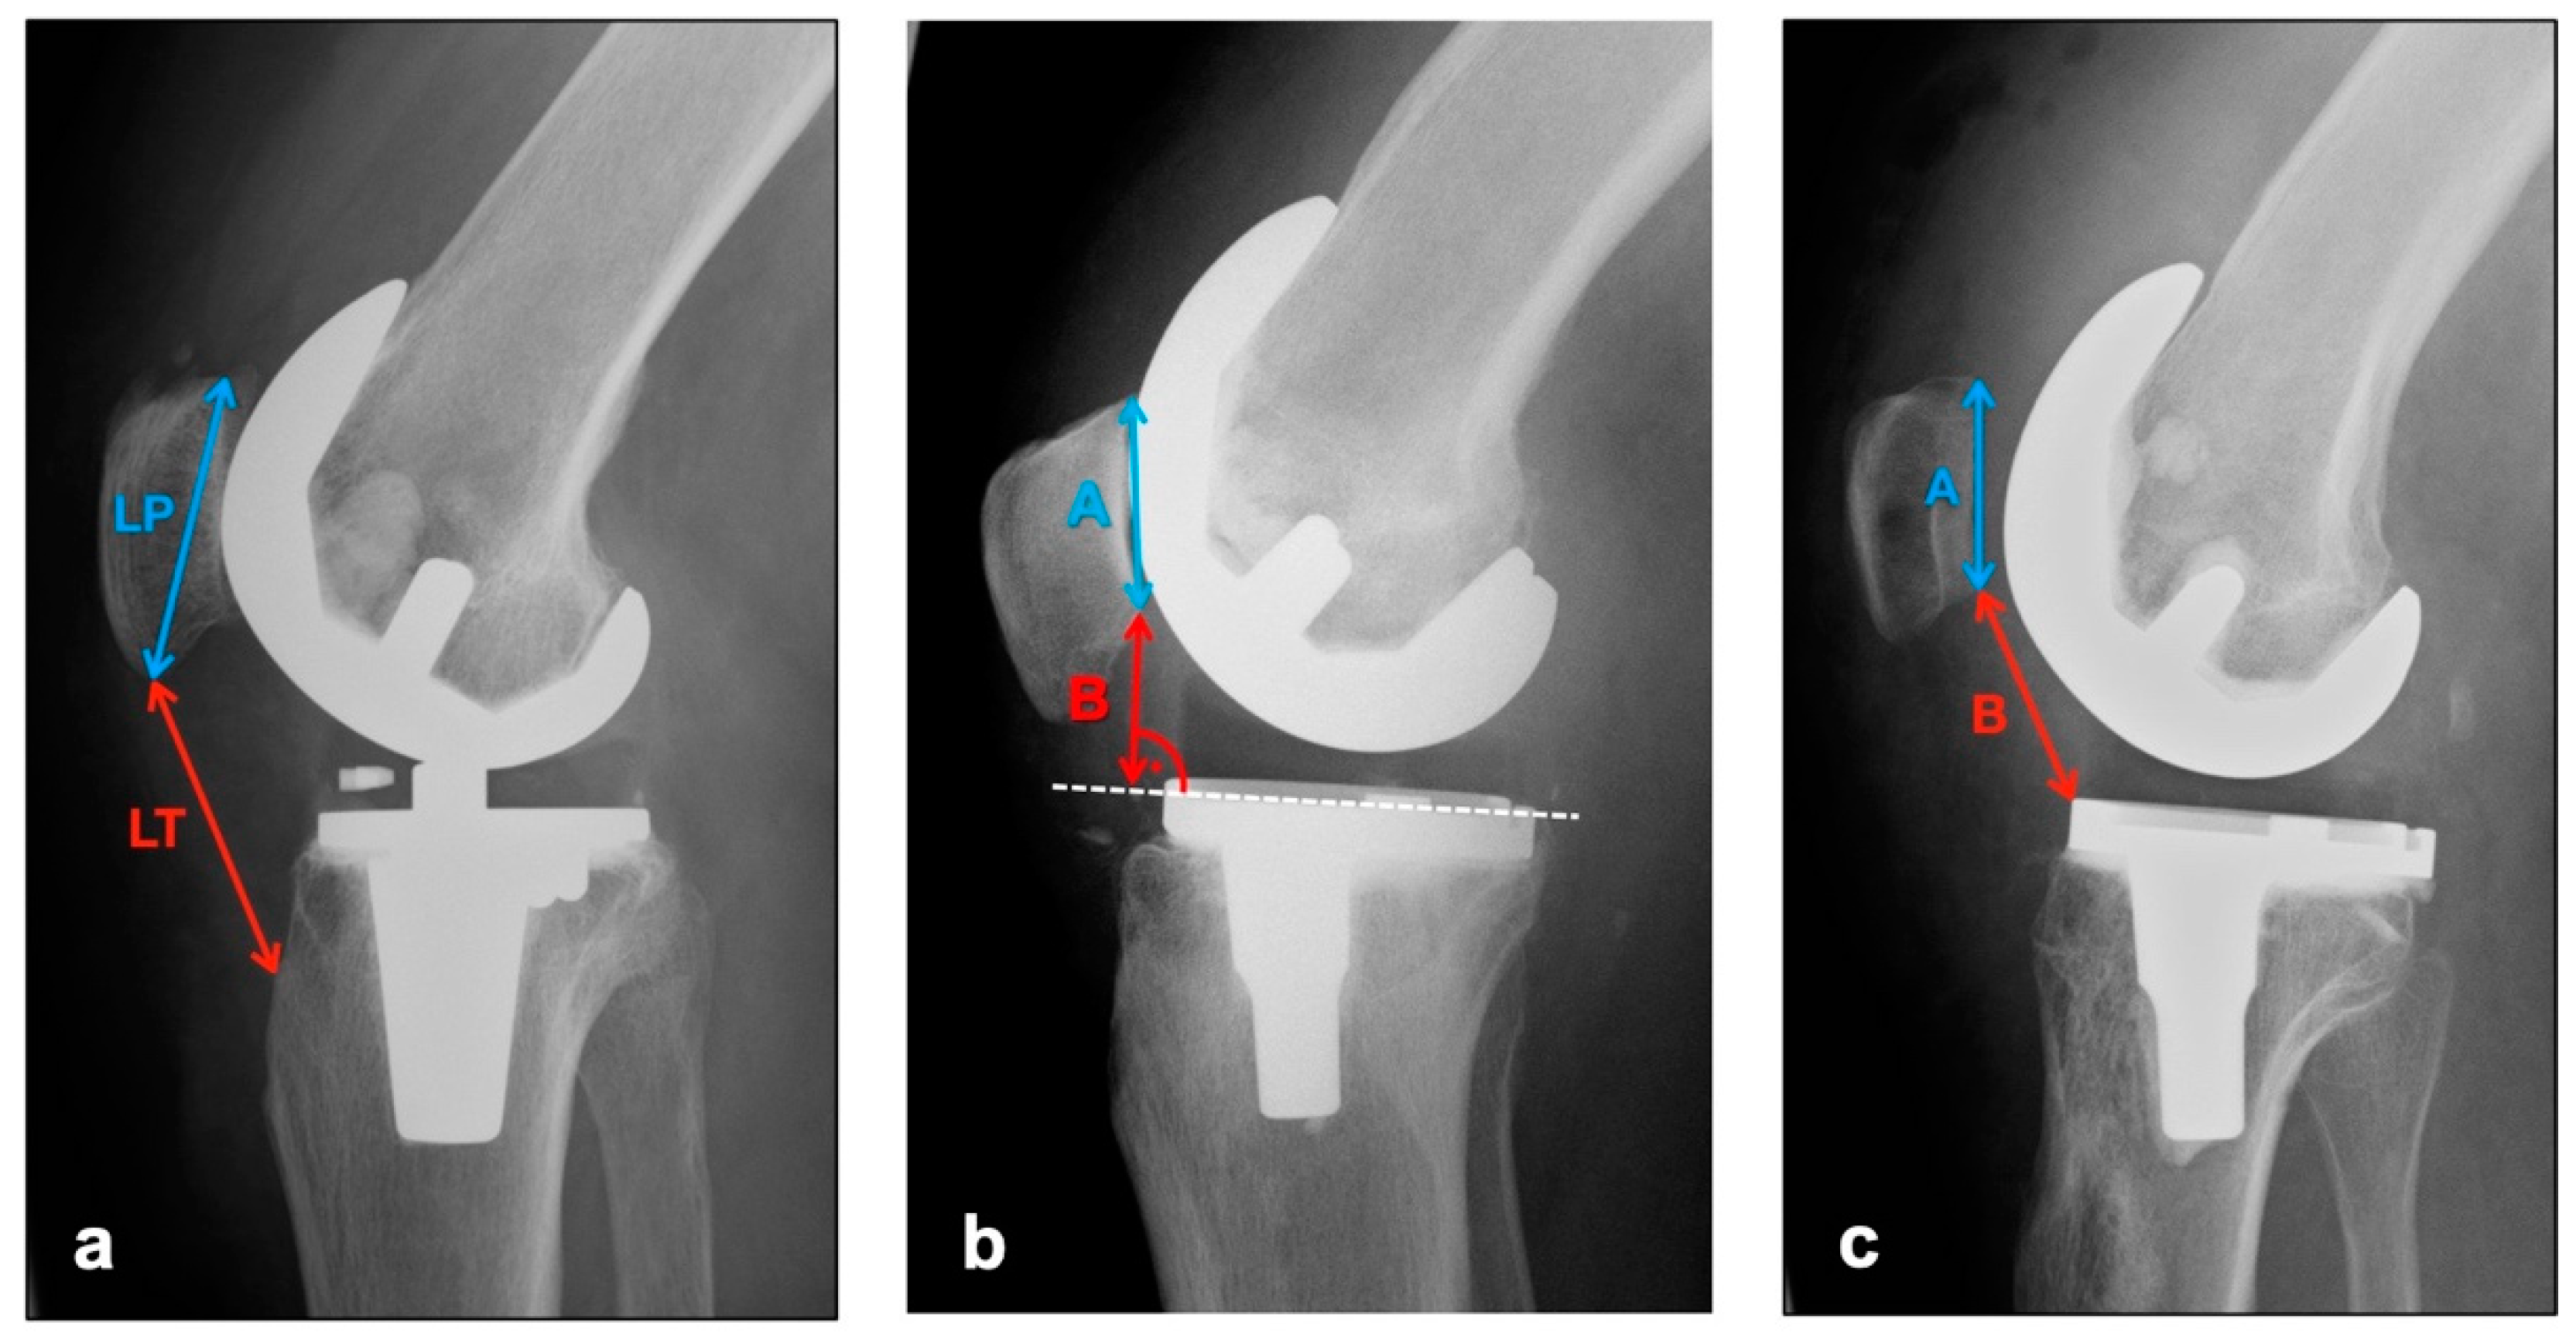

The images in lateral projection with knee flexion between 30° and 45° (dependent on patient compliance and experience of technical assistant) were used to assess vertical positional deviations of the patella cranially (patella alta) or caudally (patella infera). Three different indices were measured (see Figure 1).

Figure 1.

Measurement of patellar height with (a) Insall–Salvati Index (Quotient LT/LP), (b) Blackburne–Peel Index (Quotient B/A), (c) Caton–Deschamps Index (Quotient B/A).

The Insall–Salvati Index, which is largely independent from the joint position, is calculated as the quotient of the distance between the poles of the patella and the length of the ligamentum patellae from the caudal patellar pole to the insertion at the tibial tuberosity [17]. Normal range is 0.8–1.2 [18].

Instead of the pole distance, the Blackburne–Peel Index measures the articulating surface of the patella and relates it to a perpendicular from the lower pole of the patellar articulating surface to the tibial plateau [19]. Normal range is 0.6–1 [18].

The Caton–Deschamps Index is measured in a similar way, but instead of the previously described perpendicular, the distance from the caudal pole of the patellar articulation surface to the ventrocranial boundary edge of the tibia is measured and set in relation to the patellar articulation surface [20]. Normal range is 0.6–1.2 [18].